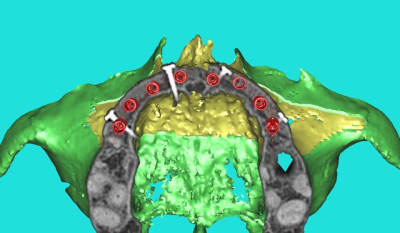

3D secteur 1

Comment simplifier et fiabiliser les greffes cas clinique dr pxav 1 to7kuq - Eugenol

Comment simplifier et fiabiliser les greffes cas clinique dr pxav 2 xckumk - Eugenol

Comment simplifier et fiabiliser les greffes cas clinique dr pxav 4 s9fhn2 - Eugenol

Comment simplifier et fiabiliser les greffes cas clinique dr pxav 5 sp6mxm - Eugenol

Comment simplifier et fiabiliser les greffes cas clinique dr pxav 6 mpweb8 - Eugenol

Comment simplifier et fiabiliser les greffes cas clinique dr pxav 7 o0oczb - Eugenol

très sympa ton montage!

la patiente va bien.